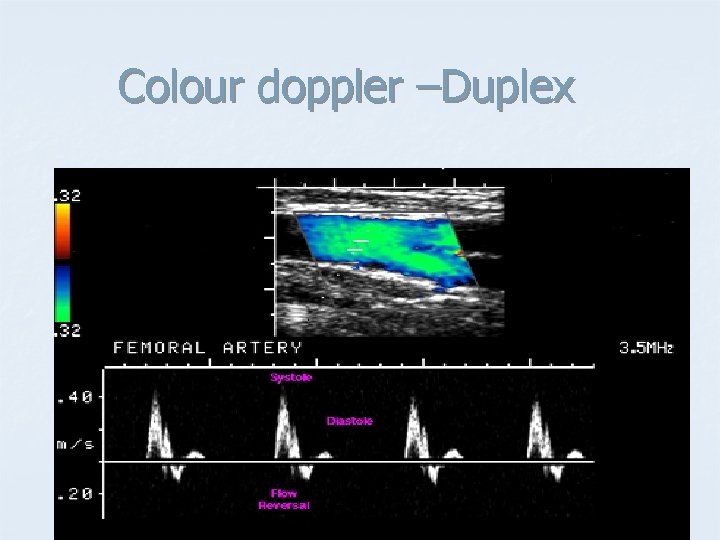

Doppler Mode. - Includes the capability of accurately measuring velocities of moving material, such as blood in arteries and veins. The principle is the same as that used in radar guns that measure the speed of a car on the highway. - Doppler capability is most often combined with Bmode scanning to produce images of blood vessels from which blood flow can be directly measured. - This technique is used extensively to investigate valve defects, arteriosclerosis and hypertension, particularly in the heart, but also in the abdominal aorta and the portal vein of the liver.

Colour doppler –Duplex